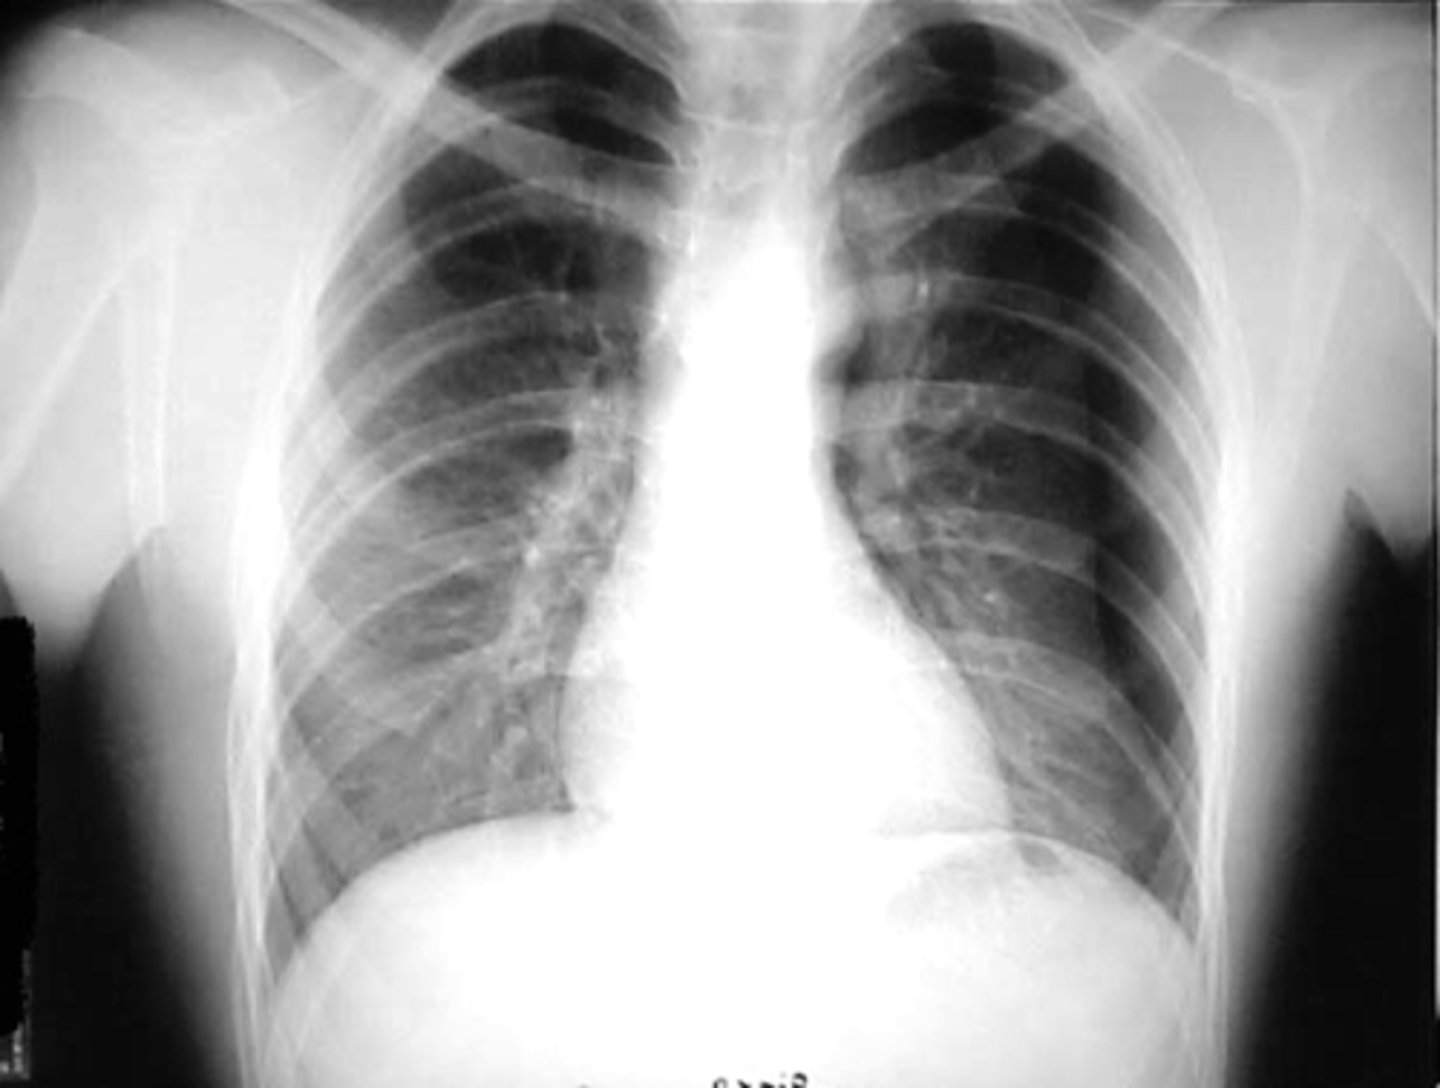

asthma

knowt flashcard image